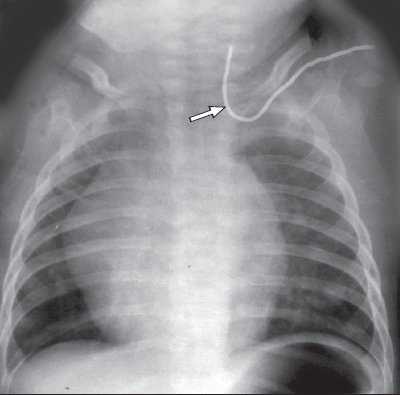

Одной из проблем при катетеризации центральных вен является корректная позиция центрального венозного катетера, при которой его конец должен находиться в полости верхней полой вены над правым предсердием. По данным отечественных и зарубежных исследователей, некорректная позиция центрального венозного катетера против тока крови встречается в 0,5-18% случаев (в 5-18% при катетеризации v. subclavia и в 0,5-5% при катетеризации v. jugularis interna). Наиболее частым вариантом некорректной позиции является расположение катетера в полости внутренней яремной вены при катетеризации одноименной подключичной вены (рис. 6). В настоящее время существует несколько методов верификации позиции центрального венозного катетера: рентгено-контроль, ЭКГ-контроль; одним из них на практике становится УЗИ для уточнения положения центрального венозного катетера (рис. 7, 8).

Рис. 6. Рентгенография. Некорректная позиция центрального венозного катетера, установленного через подключичную вену (катетер расположен против тока крови во внутренней яремной вене).